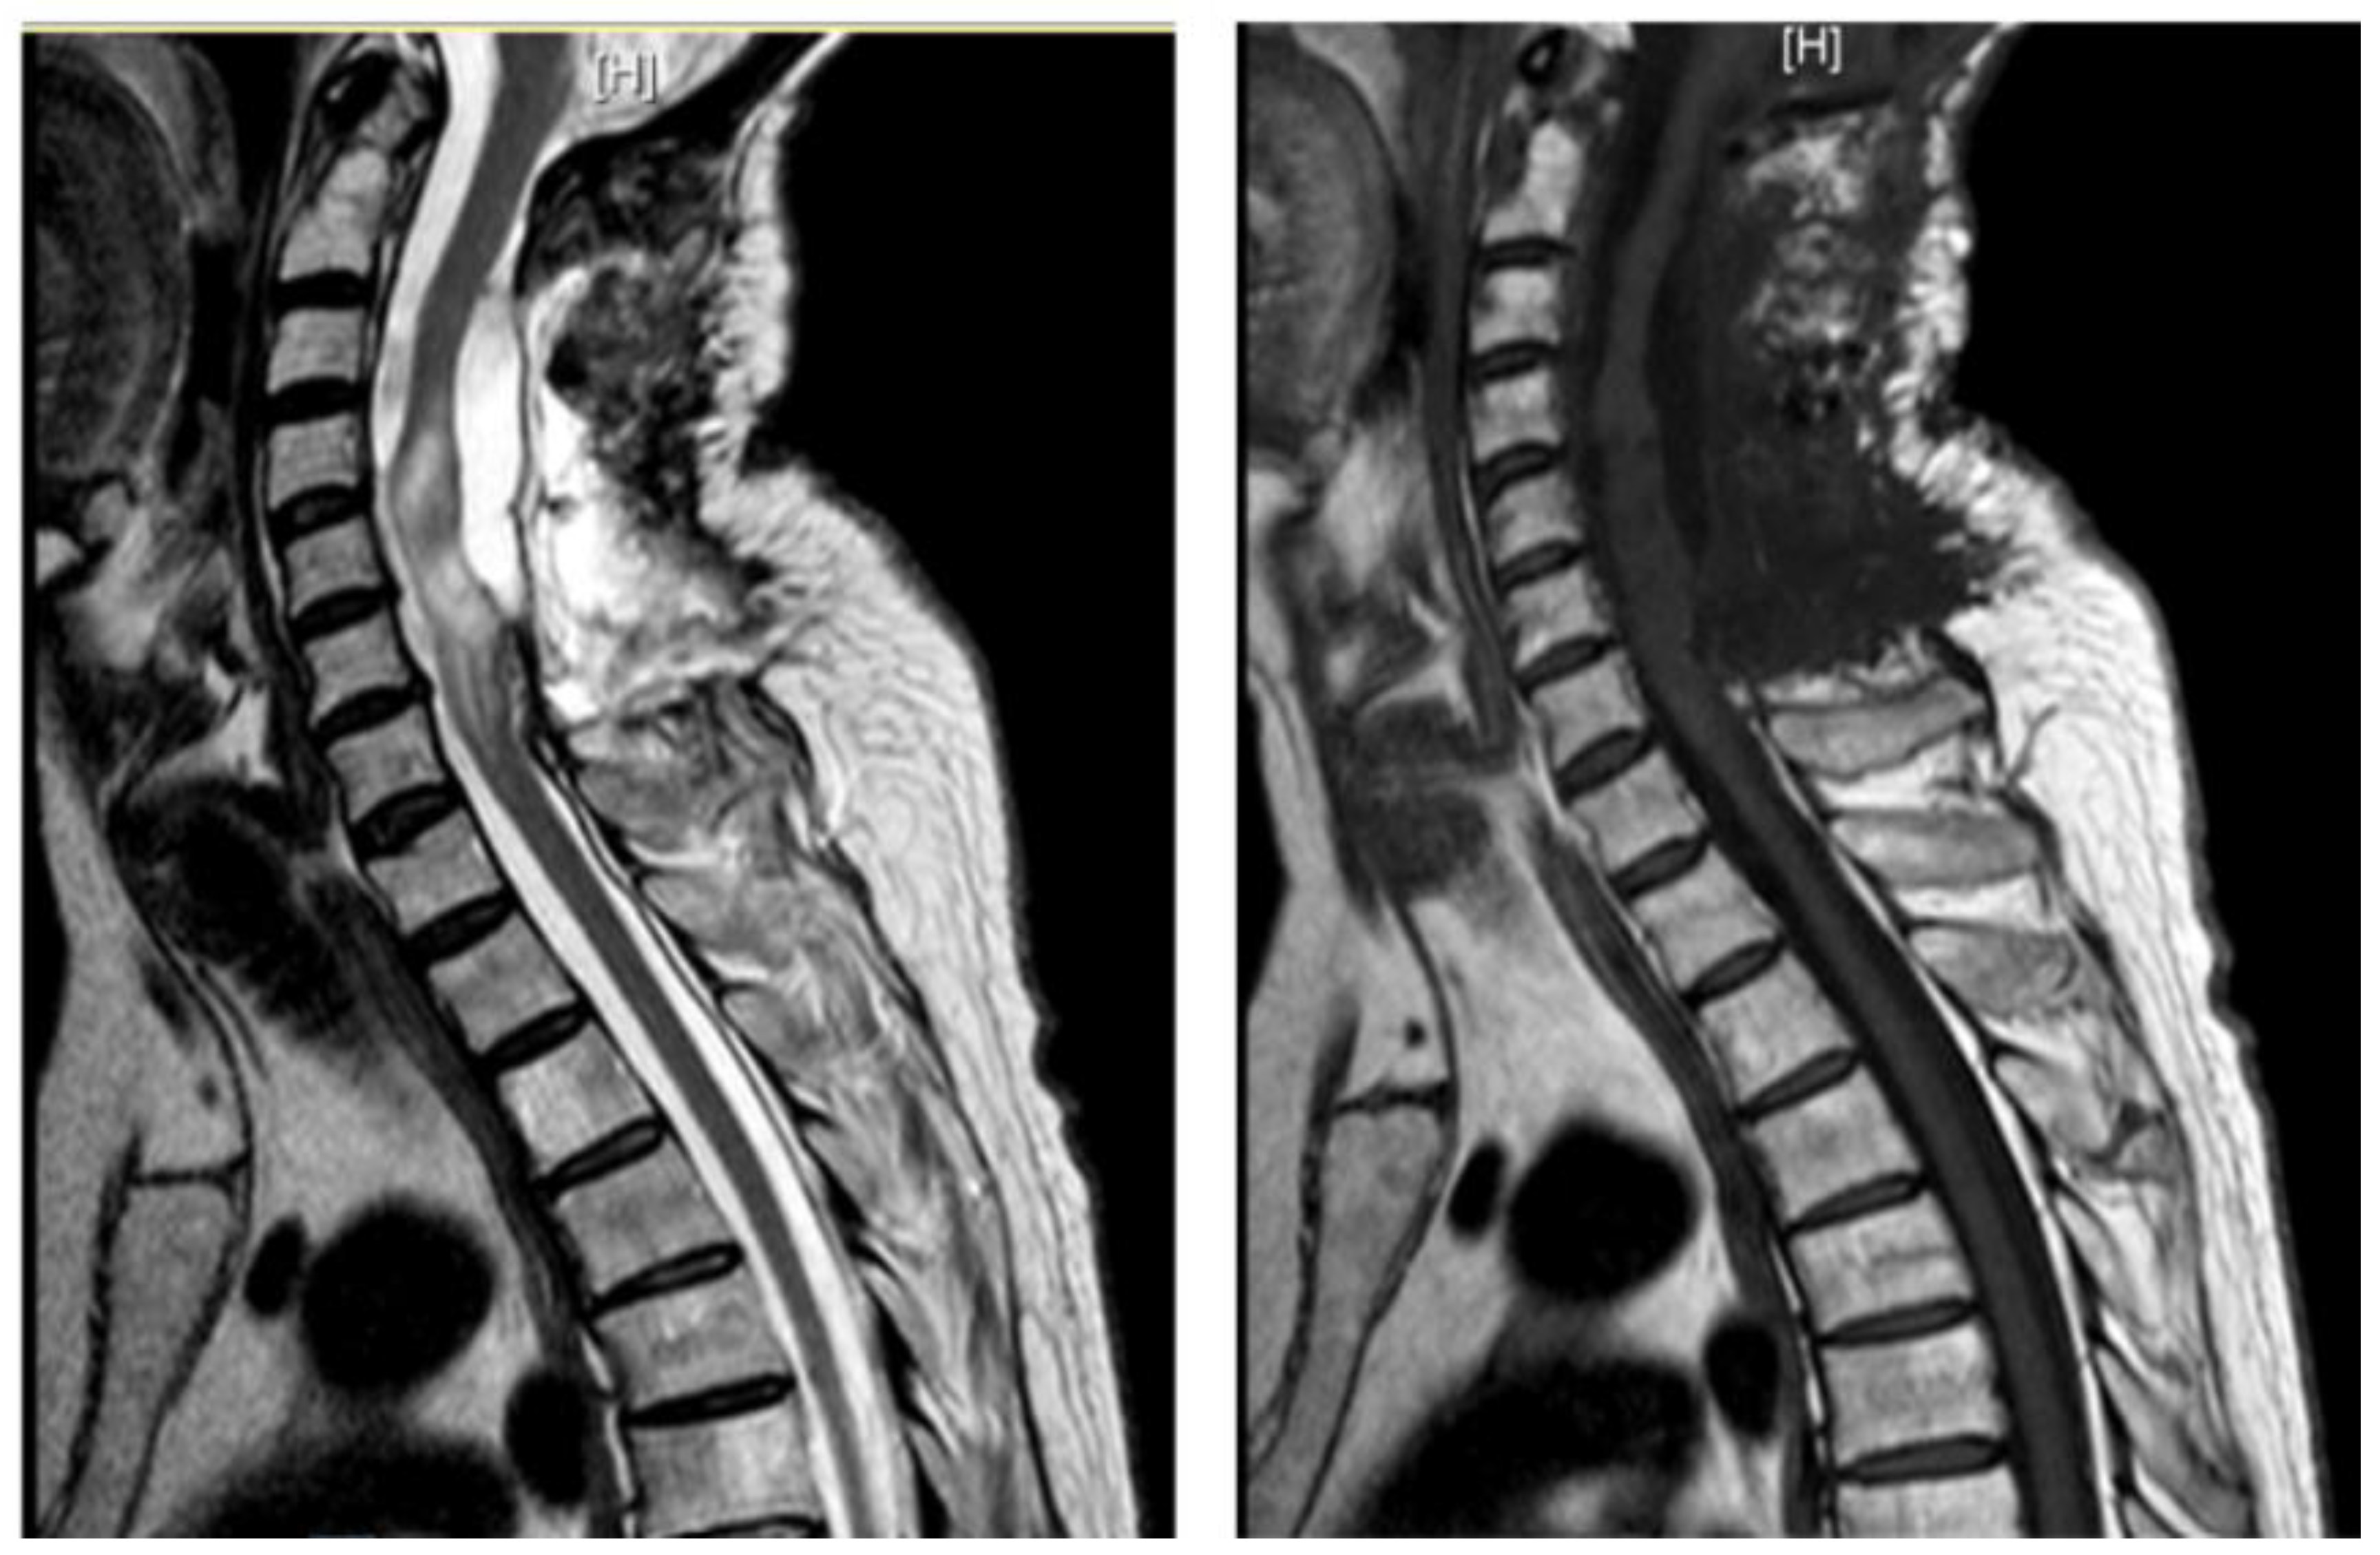

A 48-year-old man with a history of multiple neurosurgical interventions since his childhood presented with left upper limb weakness and gait worsening seven months after the removal of a cervical spinal catheter previously inserted (Torkildsen shunt). Over the next five months, his condition deteriorated, resulting in an inability to walk independently. Neurological examination revealed left upper limb weakness and spastic paraparesis in the lower limbs. The MRI of the cervico-dorsal spine showed myelopathy at C5-C6 level with a dorsal cystic lesion [Figure 2]. Surgery was performed to remove the cyst and perform the lysis of arachnoid adherence. A left-sided hemilaminectomy (C5-C7) exposed and excised the cyst compressing the spinal cord. Postoperatively, the patient initially improved but later developed tetraparesis. The MRI performed two months later showed persistent cord swelling and myelopathy extending to D1-D2 [Figure 3]. A second surgery included decompressive laminectomy (C6-C7) and removal of intradural adhesions. Despite these interventions, the patient’s tetraparesis remained stable with slight upper limb improvement. Follow-up MRI revealed ongoing signal changes from C3-C4 to D4-D5. A third surgery revealed intraoperatively new arachnoid adhesions and included an exploratory biopsy. Despite no further neurological decline, MRI continued to show persistent intramedullary signal abnormalities at three-year follow-up.

Figure 2. Case 2: pre-operative MRI (left) and post-operative MRI (right).

Figure 3. Case 2: pre- and post-operative MRI showing reduction of the myelopathy area.